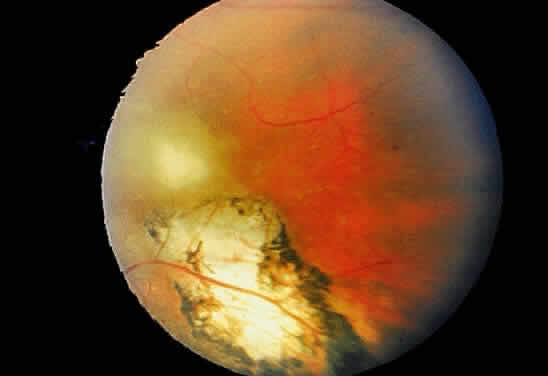

Bradyzoites are slowly metabolizing organisms found in cysts formed within the tissue of the infected host. The size of the Toxoplasma cyst varies, depending on the number of organisms that have multiplied within it. The cyst may reach more than 100 μm in diameter and may contain from 50 to 3000 organisms. The cyst wall is strongly argyrophilic and periodic acid-Schiff positive. It contains constituents that are derived from both the parasite and the host tissue. Constituent from the host tissue compose the outer part of the cyst, whereas those derived from the parasite are in the inner part of the cyst wall. Toxoplasmosis may be found in the inner layers of the retina after episodes of acute retinochoroiditis. The cyst may stay in the retinal tissue for years without showing any signs of invasiveness. Considering that the tissue cyst incorporates elements derived from the host into its outer wall, it is easily tolerated by the host, and no inflammatory reaction is seen around it (Fig. 2). It may remain for years in certain tissues, such as the eye or muscles, without provoking any inflammatory reactions. The bradyzoite inside the cyst derives its nutrition from the slow diffusion of substances through the cyst wall. The number of organisms increases within the cyst in the retina, and once the cyst wall breaks down by mechanical stretching, the bradyzoites escape, convert into tachyzoites, and invade contiguous cells. This process may lead to recurrence of retinitis. Certain immunologic mechanisms of the host may influence the organisms significantly. Immunosuppression coinciding with the rupture of the cyst and release of bradyzoites allows the organisms to become tachyzoites and proliferate in host tissue without restriction. The cyst of the Toxoplasma organism appears to be a defensive stage in its life cycle. The resistance of toxoplasmosis within chronically infected tissues of animals may lead to transmission of the disease by the ingestion of undercooked meat, including mutton, beef, pork, and chicken. Tissue cysts can develop within any organ and are commonly found in infected tissues of brain, eye, heart, skeletal muscles, and lymph nodes. Rupture of tissue cysts causes reactivation of the systemic toxoplasmosis in immune deficiency states, leading to dissemination of Toxoplasma organisms to other organs.